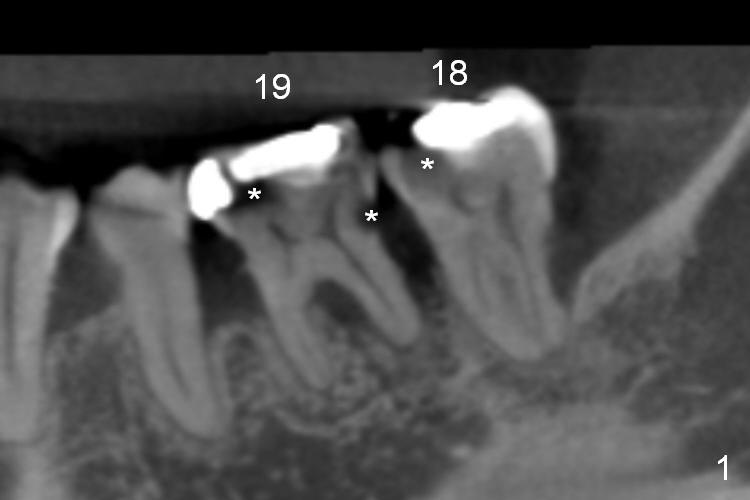

A 48-year-old lady (HJ) has several missing teeth (UL, UR, LR).  Suddenly there is pain from LL quadrant, either due to caries (Fig.1 *), periodontitis or both.  Conservative treatment (RCT) should be tried first.  If one of the teeth is deemed non-salvageable, extraction and immediate implant is provided (Fig.2,3 (B: buccal, L: lingual)).  Clindamycin will be used for socket disinfection.